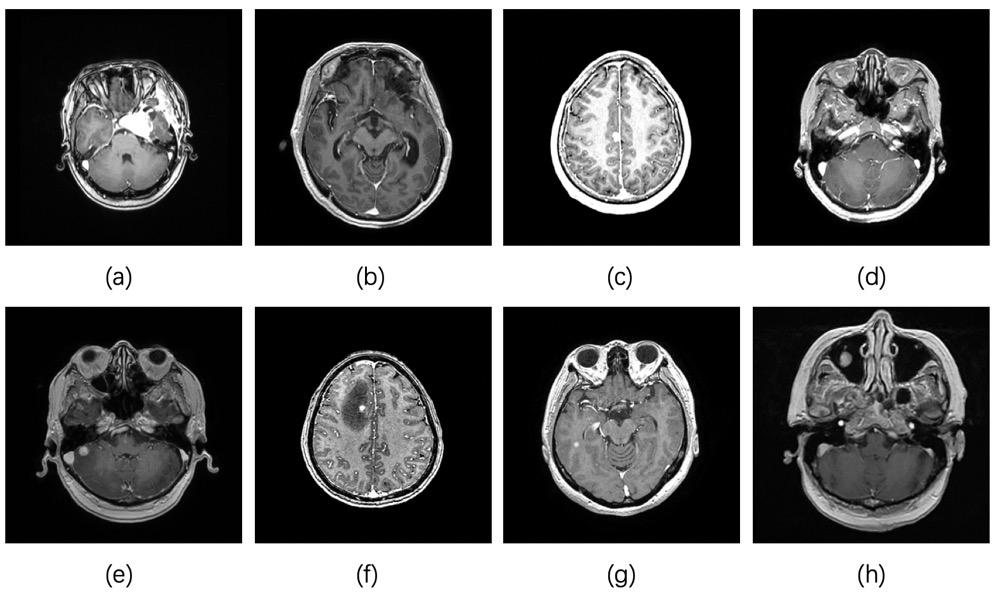

In this paper, we used the new brain MR dataset provided by Ruijin Hospital, Shanghai Jiao Tong University School of Medicine. All experiments were performed in compliance with the Declaration of Helsinki. Written informed consent was acquired from each patient or next of kin. Patients underwent MR scans on a 3T scanner using a 16-channel head coil in a supine position. In order to facilitate the therapeutic planning and treatment of GKRS, a gamma knife rigid head frame (Elekta, Stockholm, Sweden), which was matched with the head coil, was fixed on patient’s head. The T1 MPRAGE sequence was performed on all of the patients 5 minutes after administration of 0.1 mmol/kg body weight of contrast agent (Gadoxetic Acid Disodium Injection, Primovist, Bayer Vital GmbH, Leverkusen, Germany). The dataset contains 3670 T1 MPRAGE sequence brain MRI’s images and includes 7 types of tumors: cavernous hemangioma, glioma, meningioma, acoustic neuroma, colorectal cancer brain metastasis, lung cancer brain metastasis, breast cancer brain metastasis. And it covers 70 cases, patients with brain tumors and patients without brain tumors. The physician provides complete manual annotation for each image. Table I lists the number of images of each class in the dataset. Figure 1 shows a sample of various tumors of the dataset used in this paper.

Refer to caption

Figure 1: Sample from the used dataset. (a) Cavernous hemangioma, (b) Glioma, (c) Meningioma, (d) Acoustic neuroma, (e) Colorectal cancer brain metastasis, (f) Lung cancer brain metastasis, (g) Breast cancer brain metastasis, (h) No tumor.